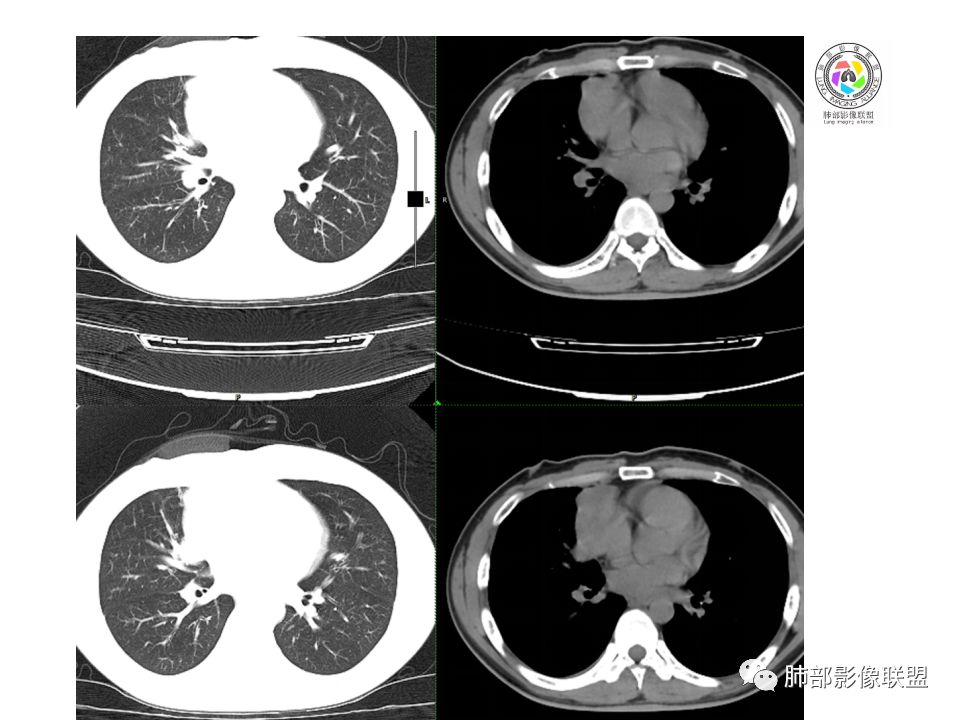

晨读:前纵隔占位,密度不均,沿着右侧纵膈延伸到肺门水平,周围支气管推移,大血管向内推移。临床有重症肌无力,考虑胸腺瘤可能,鉴别淋巴瘤。

患者青年人,前纵隔占位,无增强,猜一个淋巴瘤,不知道右下肺膨胀不全原因是什么

右前纵膈肿块,偏一侧生长,形态欠规则,密度不均匀,其内可见小点状钙化,双肺多发小叶中心结节及钙化灶,右侧胸膜增厚(有陈旧性结核可能),青年男性(27岁),没有增强,考虑,1,前纵隔生殖细胞瘤2,精源细胞瘤

右前上纵隔占位,瘤肺交界面清楚,提示纵隔来源,其内有点状钙化,右侧胸腔积液,有临床症状,年龄轻,考虑生殖来源可能,胸腺瘤待排,请结合临床相关检查或CT增强进一步检查。

前纵隔占位,伴点状钙化;上腔静脉后移位。伴右胸膜局限性增厚,临床有重症肌无力,病人年轻,考虑胸腺瘤可能,鉴别生殖源性肿瘤。

临床症状眼睑下垂,右纵膈占位,偏向一侧,有分叶,跟上腔静脉边界不清,淋巴结肿大,考虑胸腺瘤或胸腺癌

右前纵隔占位,有分隔`低密度、点状钙化,边缘光滑,侵袭心包不明确,伴右胸少量积水,考虑恶性,生殖源性可能大,有视物不清,是否脑转移待查。建议HCG丶AFP检查。鉴别1:胸腺瘤、癌,30一40岁以下,少见,但有眼脸下垂,肌无力,待排除。2:淋巴瘤:侵袭性不强,有点状钙化,不支持。3:畸胎瘤:有低密度丶钙化,建议增强进一步明确。4:神经源性:一般后纵隔常见,不支持。5:LCD:症状少见,可以有树枝状钙化,浆细胞型可以有低密度,增强进一步明确

前纵隔偏侧肿块,病灶内见点状钙化,症状肌无力,考虑恶性,胸腺瘤或神经内分泌癌

没有增强,好像两个病灶,上方三角形的像是胸腺增生。下方肿块,没有增强显得更难了,微钙化,轻度分叶,像有坏死低密度影,右侧少量胸水,胸膜受侵.,有视物模糊眼睑下垂。考虑胸腺瘤B1型及以上、B2型可能或生殖细胞瘤

患者年轻,有肌无力症状,除肿块外,前纵隔密度增高,与心包界限不清,考虑恶性。

前纵隔右区占位性病变,上区与胸腺延续,下区呈分叶状,尽管年龄<30还是首先考虑胸腺瘤,侵袭性可能性大(眼睑下垂不知是否有关)。鉴别主要是生殖细胞类肿瘤,主要是精原细胞瘤。另左肺上叶结核球,右侧胸腔积液,需除外结核性胸膜炎和转移

前纵隔占位性病变,偏向一侧生长,密度不均,可见点状钙化,考虑胸腺瘤,鉴别精原细胞瘤

右前上纵膈肿块,内有点状钙化和少许小片状坏死,局部边界似欠清,右侧胸膜腔少量积液,年轻男性,小于30岁,有重症肌无力,虽然年龄偏轻,仍先考虑胸腺瘤,代排生殖源性肿瘤

晨读前纵隔肿块,偏右侧,密度不均,见点状钙化灶及分隔状低密度影。胸腺瘤>生殖细胞瘤>淋巴瘤

前纵膈占位,上腔静脉受推移,有分叶密度较均匀,结合临床考虑胸腺瘤,待排生殖细泡瘤.淋巴瘤

前中纵隔(胸腺癌区)不规则肿块,密度不均,有坏死区、点状钙化,边缘不会整肿块偏向右侧,向心包流注感,右胸腔少量积水。患者27岁,重症肌无力表现。